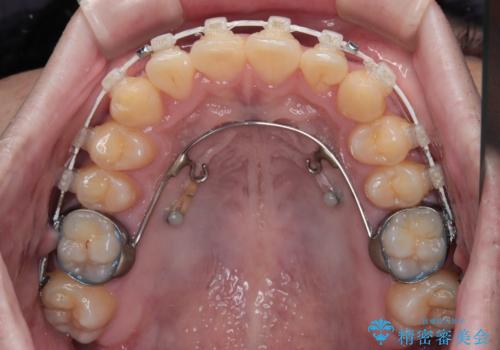

- 上下前歯の捻れやデコボコを気にして来院された患者様です。

マウスピース矯正でもワイヤー矯正でも対応可能でしたが、極力楽をして治したいとのことでワイヤー装置にて治療をおこなうこととしました。

口元はそれほど突出しておらず、患者様自身も気にしていらっしゃいませんでしたが、前歯の捻れやデコボコを解消すると、前方に拡大され、治療後に出っ歯仕上がりとなるリスクがあったため、補助装置により上顎臼歯を後方移動していくこととしました。

昼休みを活用して通院してくださり、1年半であっという間に終えることができました。